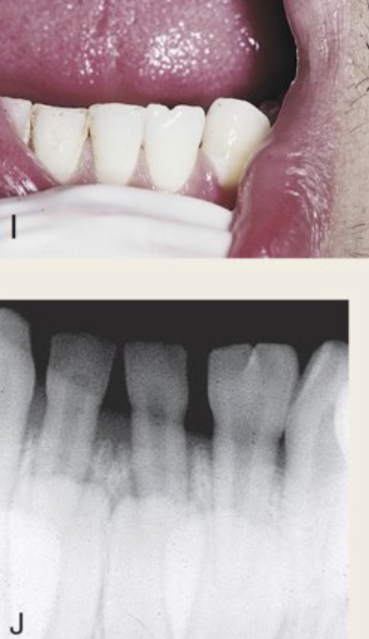

Gemination (I,J)

Tooth germ tries to divide and develops large single-rooted tooth with one pulp cavity and “twinning” commonly affecting crown of anteriors with correct number in primary or permanent dentition.

Clinical ramifications: Esthetic and spacing complications treated by orthodontic therapy